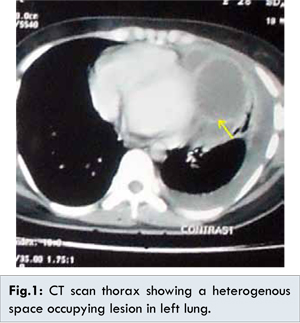

Chest X-ray revealed  a  left  sided  large  cystic  opacity.  No air fluid level was  detected.  CT  scan  thorax  showed  a  well-defined  space  occupying  lesion  measuring 16.7x11.2x9.6 cm  with  pleural  effusion  and  collapse.  The  lesion  showed  heterogenous  density  containing  soft  tissue  elements,  cystic  areas  and  foci  of  calcifications.  Perilesional inflammatory change and thickening was noted.  No mediastinal lymphadenopathy was seen [Fig.1]. Broncho-alveolar  lavage  fluid  examination  showed  scanty  mature  squamous  cells  and  cluster  of  bronchoepithelial  cells  without  any  evidence  of  dysplasia. Fibreoptic  bronchoscopy  under  local anaesthesia  revealed  external  compression  at  the  level  of  left intermediate  bronchus.  No intrabronchial  mass  or  inflamed  area was  noticed. Pulmonary  function  test  showed  decreased  FVC  and  25%-75% PEF  indicating  small airway  obstruction.

Radiologically  it  may  appear  as  a  cavitary  lesion,  consolidation  or  as  a  heterogenous space  occupying  lesion  as  seen  in  this  case  containing  various  elements  like  fat,  fluid and  foci  of  calcification [3]. Since  intrapulmonary  teratoma  is  a  rare  tumor,  initially  a provisional  diagnosis  of  hydatid  cyst  was  made  in  our  case.  Later  on  after  doing  CT  scan  and  excision  of  the  tumor  followed  by  histopathological  examination  the diagnosis  was  confirmed.